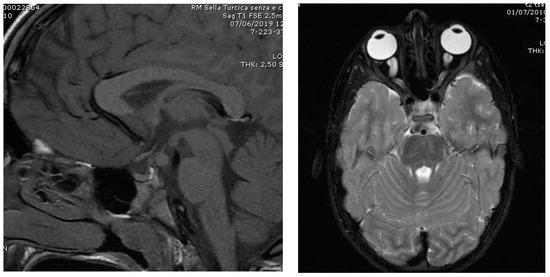

| CNS abnormalities: |

| Hypothalamic hamartoma |